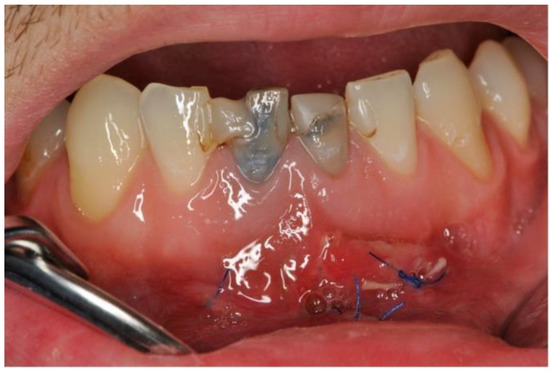

2. Case Description

3. Clinical Procedure and Outcome